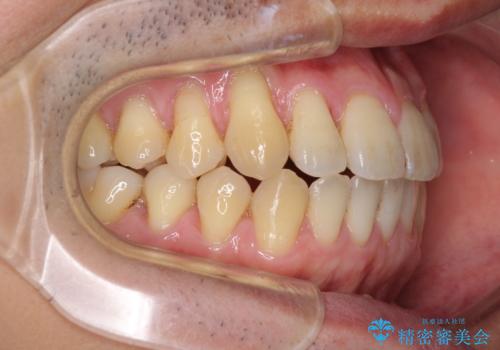

- 上下の前歯の反対咬合を気にして来院された患者様です。

インビザラインを用い、下顎はIPR(歯と歯の間を削る)と歯列全体を後方に移動させ、上顎は前歯を持ち上げることで、反対咬合を改善していくこととしました。

八重歯の歯根が見えている点も気になっているので、矯正歯科治療後に歯肉移植による根面被覆を行うこととしました。